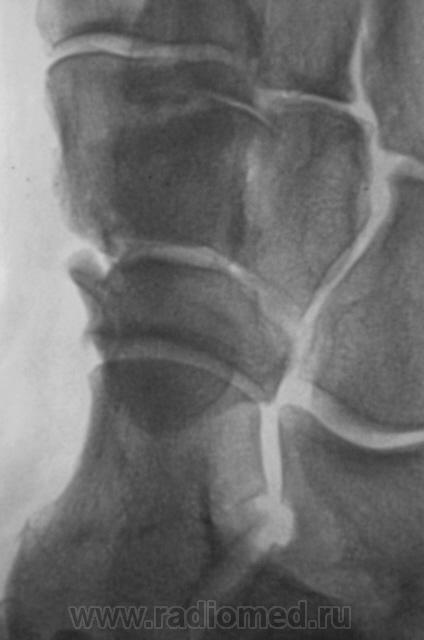

Экзостоз ладьевидной кости?

Да, похоже на 2 остеомы на широких ножках.